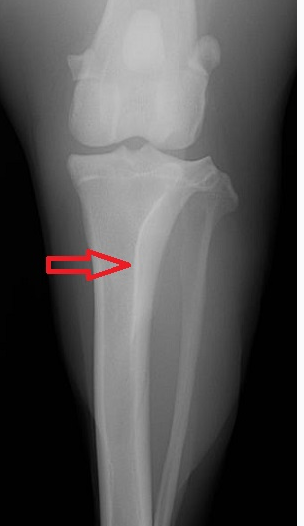

Red arrow- 4th tarsal bone

blue arrow- lateral malleolus, also the origin of the Peroneus longus m. and Lateral digital extensor m.

Tibial crest